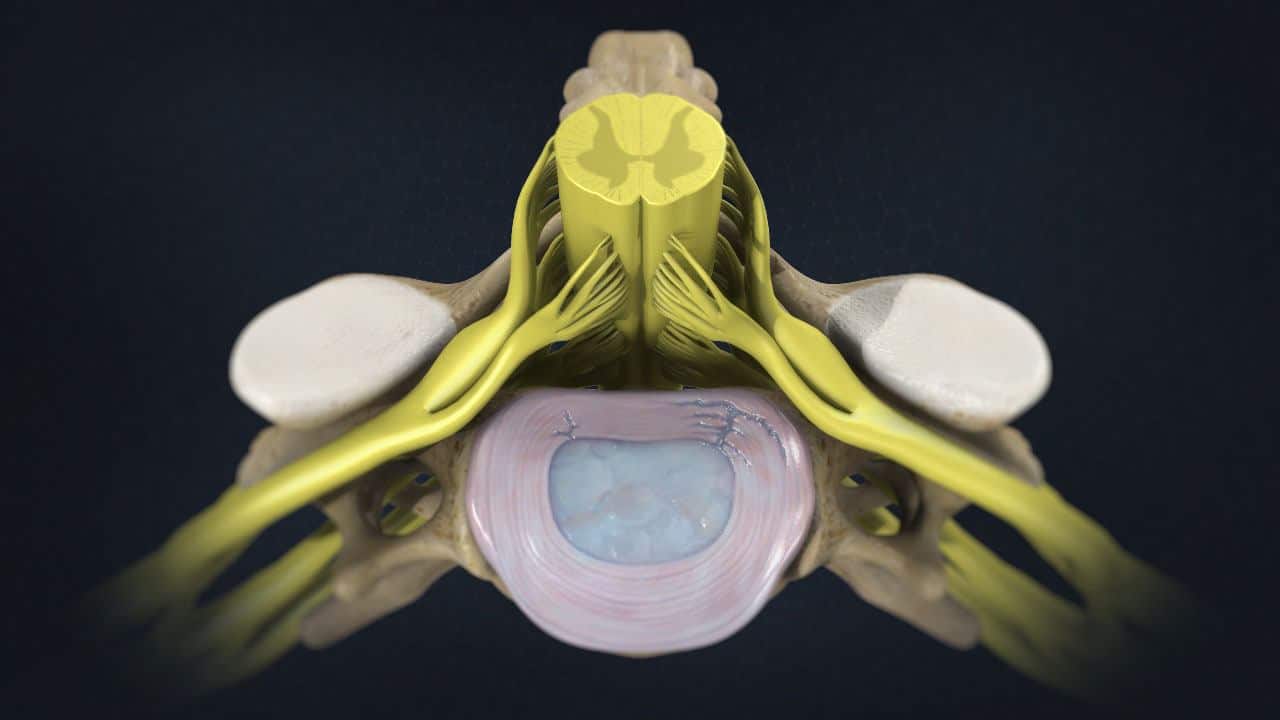

Disc herniation injury Chiropractor How To Heal Annular Disc Tear  An annular tear can be extremely painful because the outer third of the.  quick intervention for issues like annulus fibrosus tears or annular tear lumbar spine can significantly improve outcomes and shorten annular tear recovery.  when a tear occurs, and no disc material is ruptured, it is called an annular tear. Outline the evaluation in patients with annular. How To Heal Annular Disc Tear.

Annular Ligament Tear How To Heal Annular Disc Tear  When there is an annular tear, the torn or extruded intervertebral disc. An annular tear can be extremely painful because the outer third of the. If these treatments do not help. Outline the evaluation in patients with annular disc tears.   healing time for annular tear varies from patient to patient.   describe the etiology, pathophysiology, and complications of annular. How To Heal Annular Disc Tear.